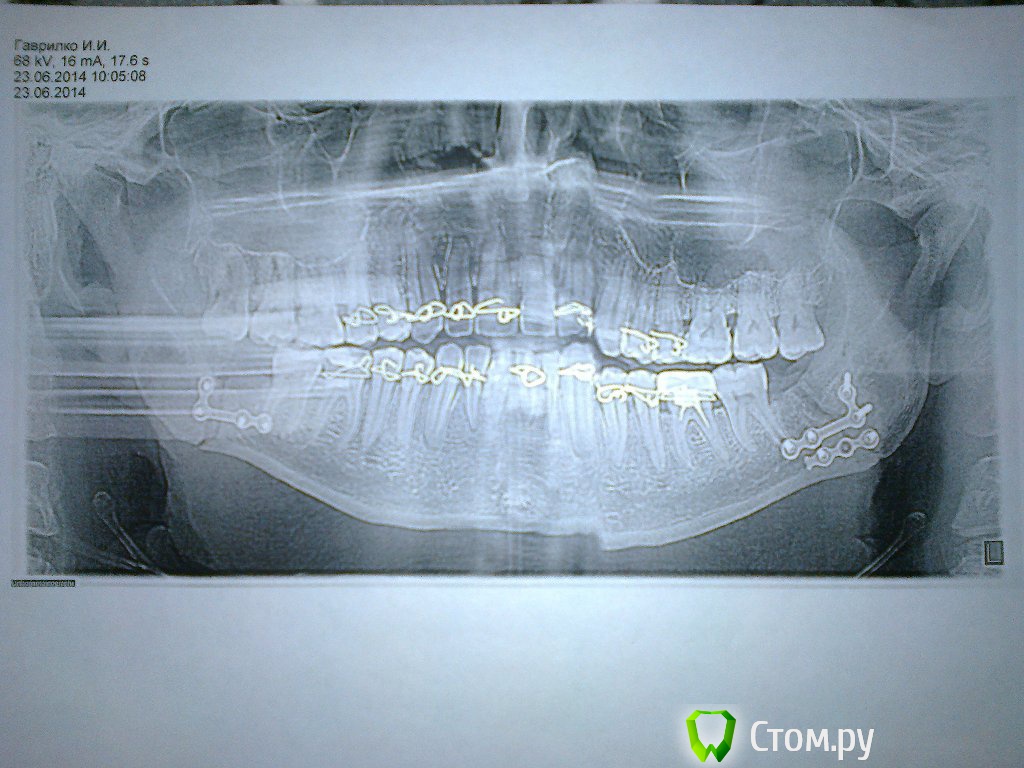

ivanich 82 Опубликовано 30 июня, 2014 Автор Поделиться Опубликовано 30 июня, 2014 Вот посмотрите снимки за 11.06. и за 23.06. Где за 23 немного дернулся при снимке, вот как по середине и съехала челюсть. Скажите, что по снимкам, все правильно сопоставлено и срастается? Ссылка на комментарий

Acidrocker Опубликовано 30 июня, 2014 Поделиться Опубликовано 30 июня, 2014 Вот посмотрите снимки за 11.06. и за 23.06. Где за 23 немного дернулся при снимке, вот как по середине и съехала челюсть. Скажите, что по снимкам, все правильно сопоставлено и срастается?По снимкам все сопоставлено замечательно. То, что посередине - дефект снимка. Ссылка на комментарий